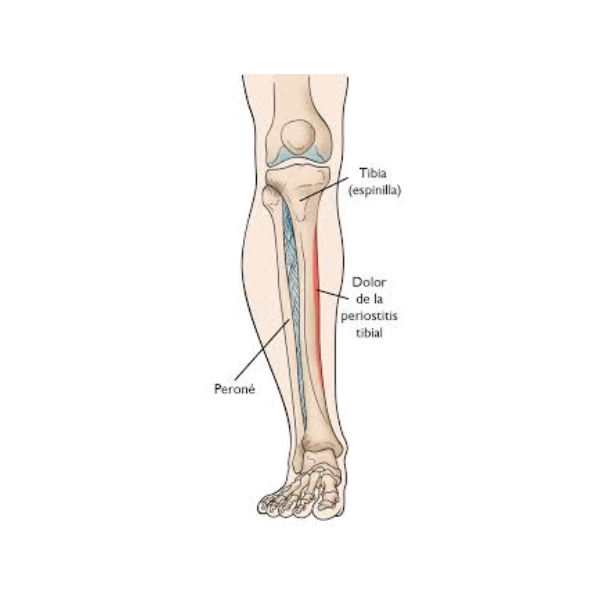

پریوستیت و سندرم شین اسپلینت

پریوستیت التهاب غشای نازک اطراف قسمت بیرونی استخوانها به نام پریوست است. این غشا برای تغذیه و ترمیم استخوان حیاتی است. این بیماری معمولاً در نتیجه ضربات طولانی مدت و مکرر به ناحیه یا فشار بیش از حد رخ میدهد. بنابراین، بیشتر در ورزشکاران، رقصندگان و افراد فعال از نظر جسمی دیده میشود.

شین اسپلینت (شین اسپلینت) یکی از شایعترین انواع پریوستیت است و به صورت درد ساق پا بروز میکند. ورزشهایی که شامل دویدن، پریدن یا توقف و شروع ناگهانی هستند، فشار روی استخوان ساق پا را افزایش میدهند و منجر به پریوستیت در این ناحیه میشوند. درد و حساسیت استخوان از بارزترین علائم این بیماری هستند.